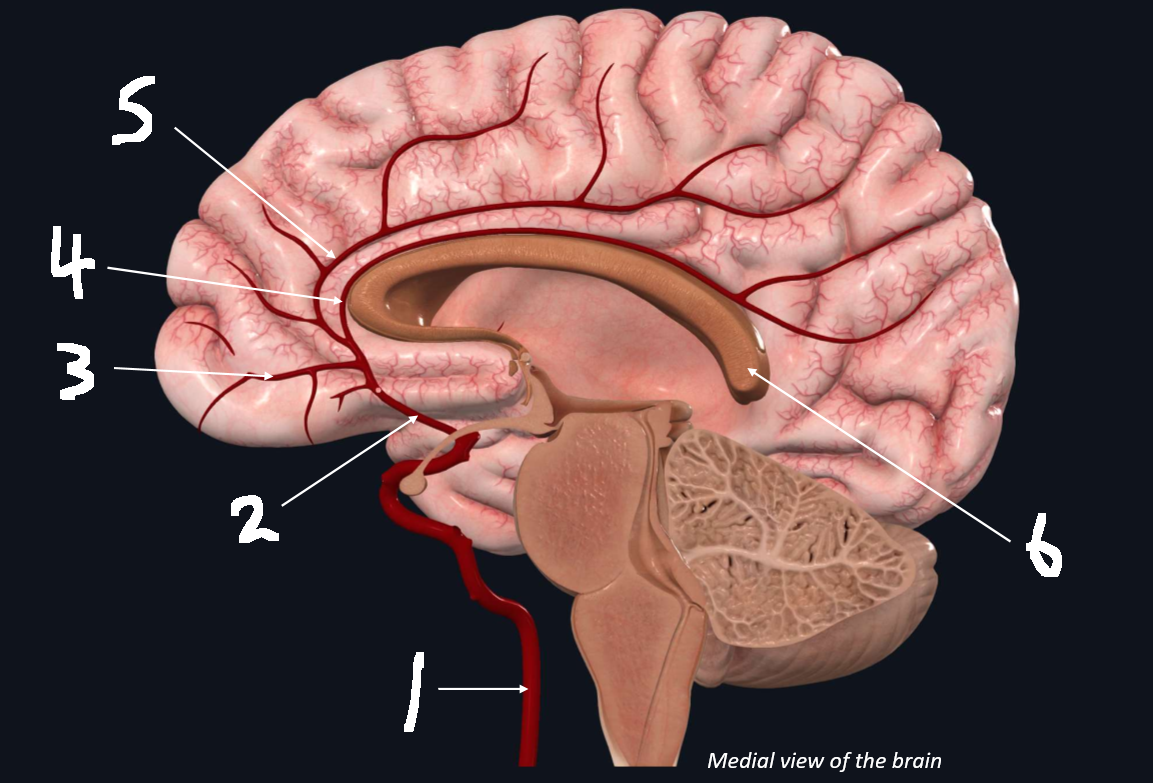

What is 1?

internal carotid artery

What is 2?

anterior cerebral artery

What is 3?

frontopolar artery

What is 4?

pericallosal artery

What is 5?

callosomarginal artery

What is 6?

corpus callosum